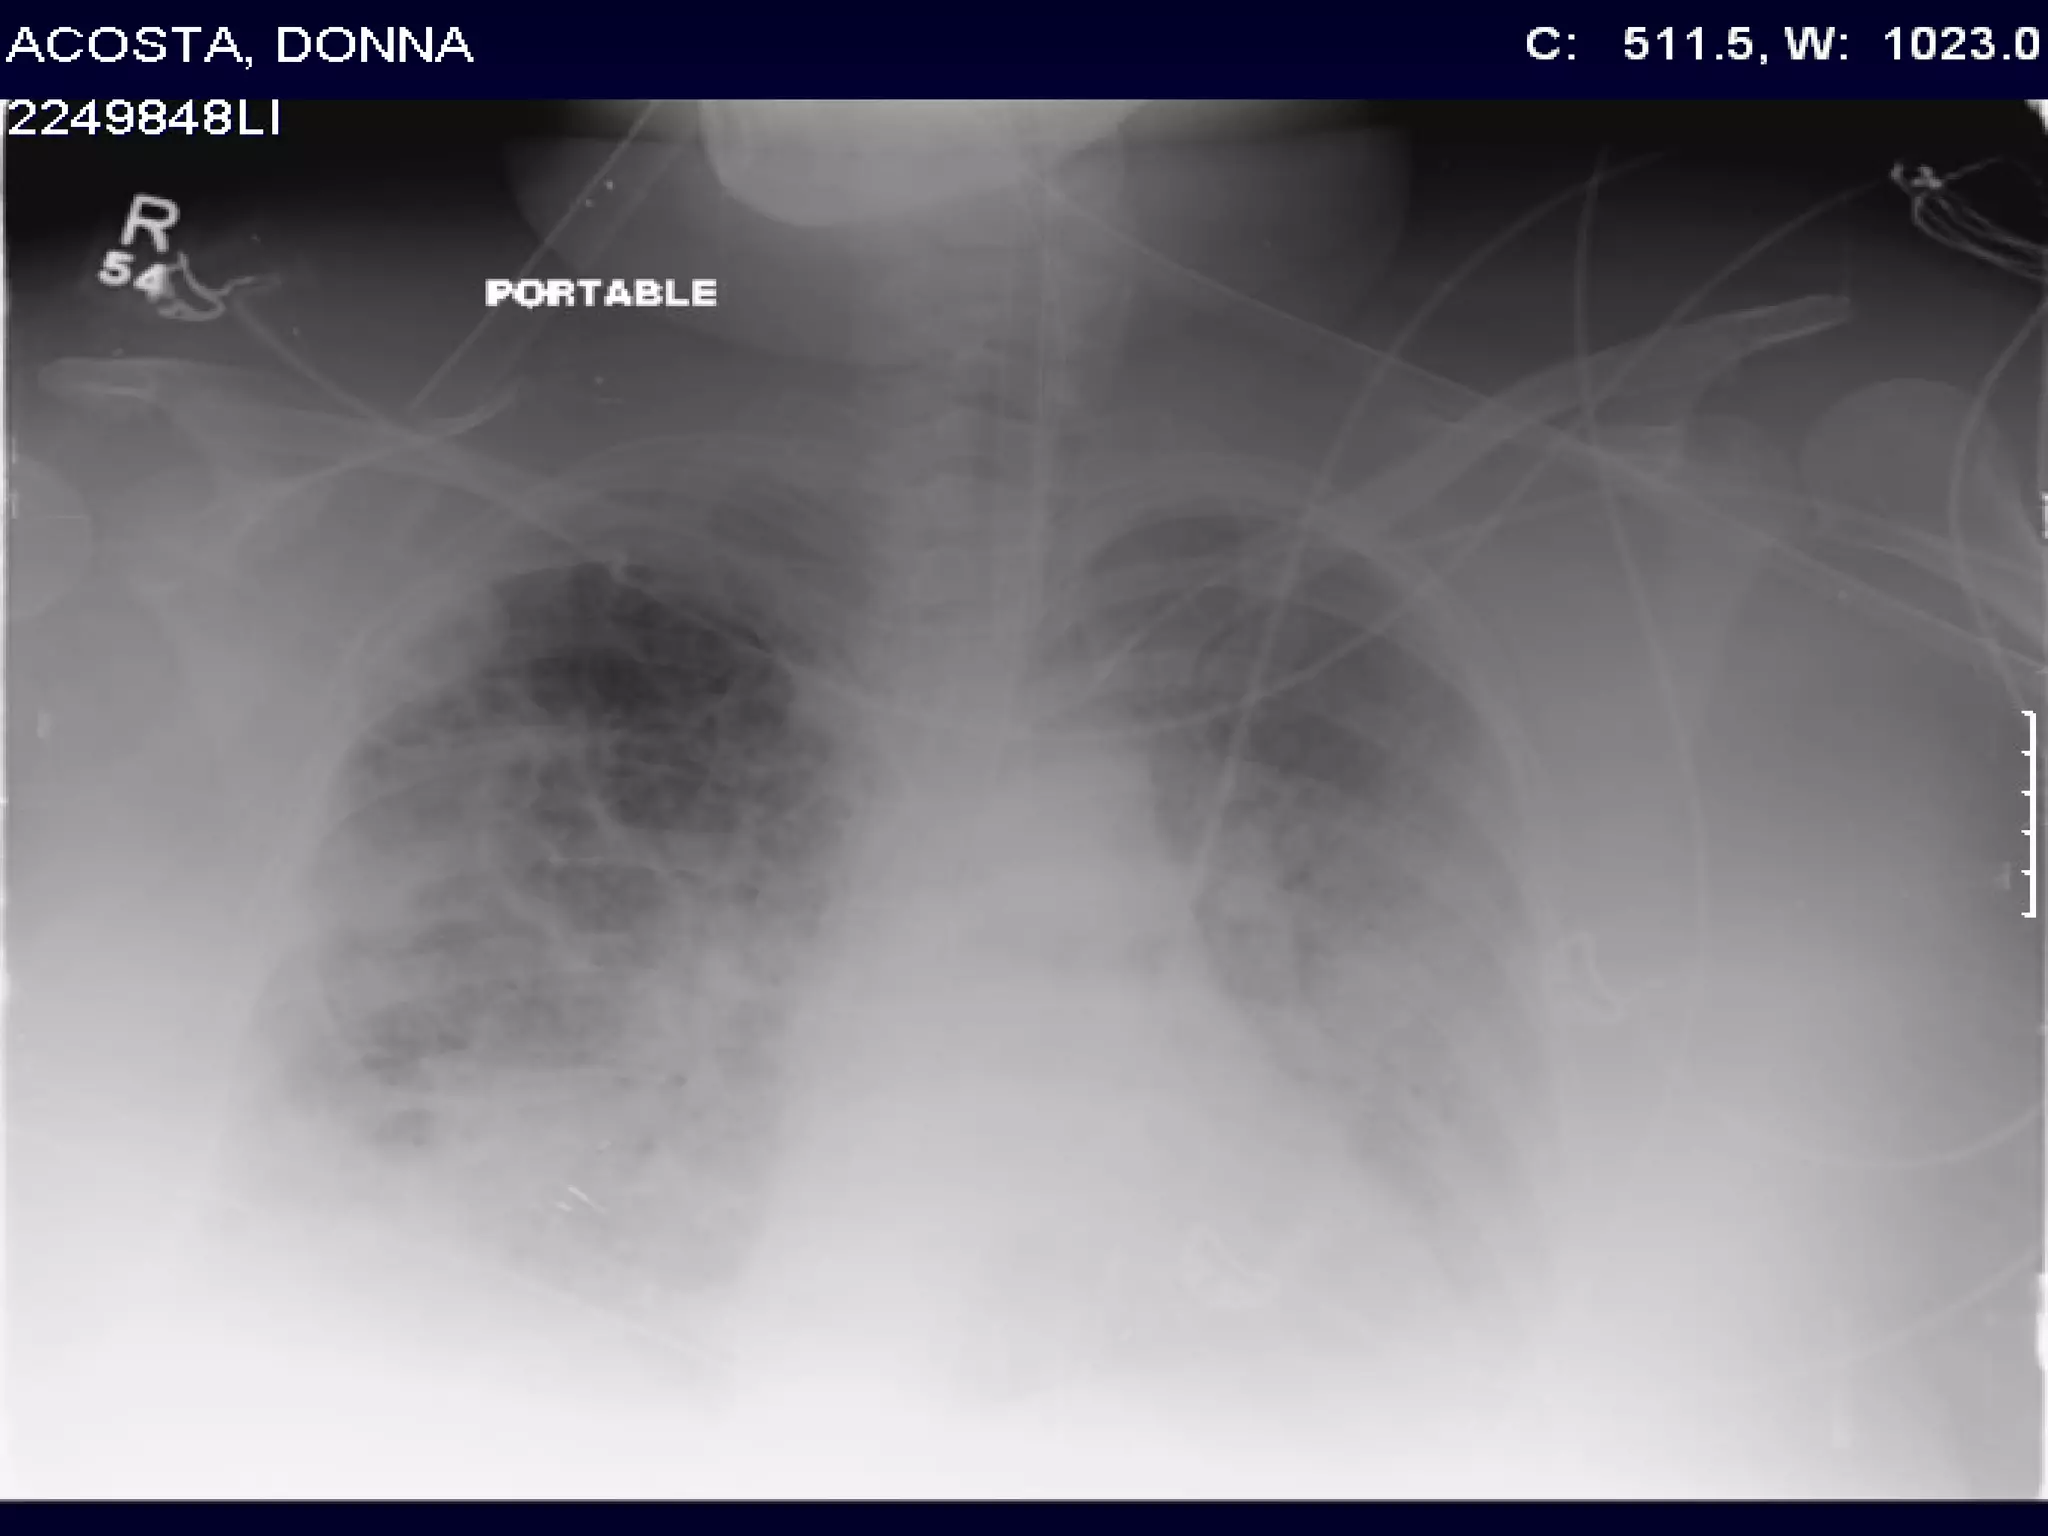

ARDS- Definition 1. PaO2/FiO2 ≤ 200  2. Bilateral (patchy, diffuse, or homogeneous) infiltrates consistent with pulmonary edema 3. No clinical evidence of left atrial hypertension ( PCWP<18)

ARDS- Definition 1.PaO2/FiO2 ≤ 200 2. Bilateral (patchy, diffuse, or homogeneous) infiltrates consistent with pulmonary edema 3. No clinical evidence of left atrial hypertension ( PCWP<18)